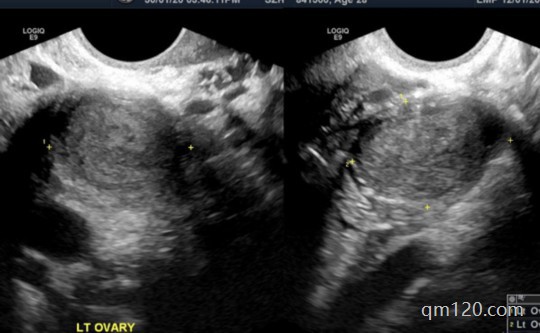

然而試管嬰兒過(guò)程中可能會(huì)遇到一些意想不到的問(wèn)題。試管姐姐將以女性在廣州進(jìn)行三代試管嬰兒過(guò)程中發(fā)現(xiàn)患有巧克力囊腫為例,探討應(yīng)對(duì)措施。一、了解巧克力囊腫:巧克力囊腫...